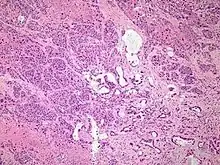

Micrograph of pancreatic ductal adenocarcinoma (the most common type of pancreatic cancer), H&E stain

Micrographs of normal pancreas, pancreatic intraepithelial neoplasia (precursors to pancreatic carcinoma) and pancreatic carcinoma, H&E stain

Histopathology

The most common form of pancreatic cancer (adenocarcinoma) is typically characterized by moderately to poorly differentiated glandular structures on microscopic examination. There is typically considerable desmoplasia or formation of a dense fibrous stroma or structural tissue consisting of a range of cell types (including myofibroblasts, macrophages, lymphocytes and mast cells) and deposited material (such as type I collagen and hyaluronic acid). This creates a tumor microenvironment that is short of blood vessels (hypovascular) and so of oxygen (tumor hypoxia).[2] It is thought that this prevents many chemotherapy drugs from reaching the tumor, as one factor making the cancer especially hard to treat.[2][3]